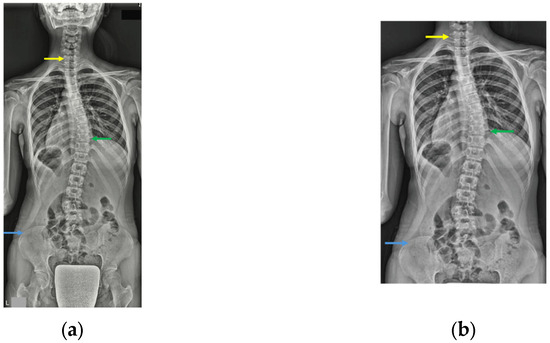

3.4. Gradient-Weighted Class Activation Mapping Attention Analysis